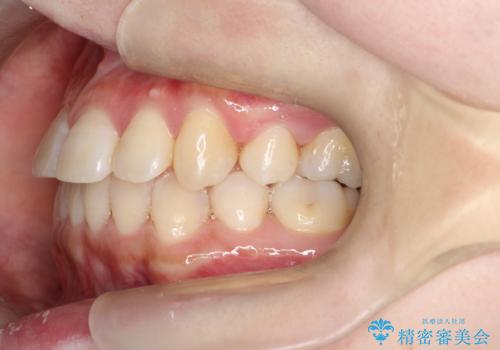

コンプレックスだった前歯のガタガタがここまで綺麗になるなんて!!

治療に関して期間こそかかってしまったものの、見た目、嚙み合わせ及び、治療期間や施術内容に大変ご満足いただきました。